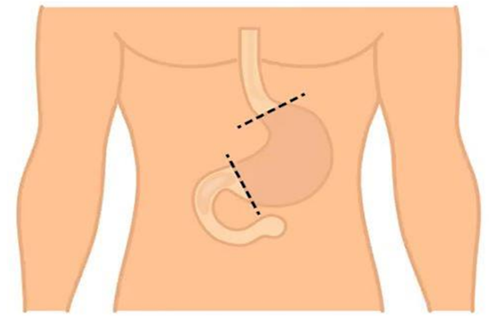

[Изображение 3] Полное удаление желудка |

Раньше для хирургического удаления рака желудка делался разрез от солнечного сплетения до пупка. В последнее время операции всё чаще проводятся через проколы в животе лапароскопическим методом или с помощью робота и 3D изображений. Метод операции определяется в зависимости от особенностей заболевания пациента. При лапароскопических операциях в сравнении с открытым методом операции восстановление проходит быстрее.